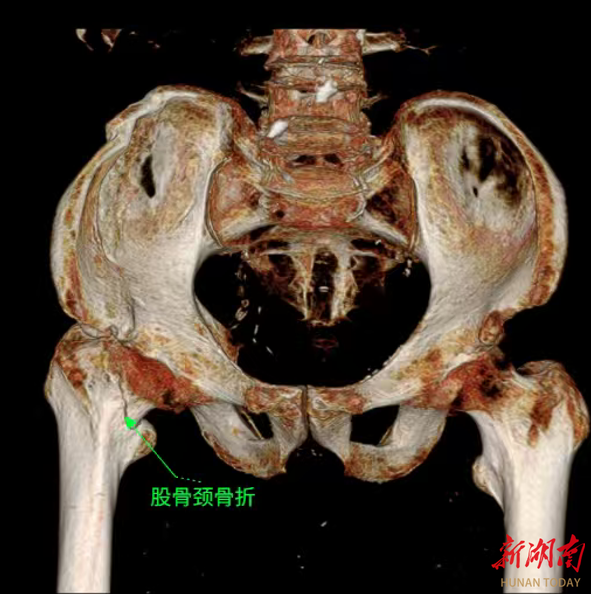

贺升建主任立即为易爷爷进行了详细的体格检查,并结合影像学检查结果,明确诊断为“陈旧性右侧股骨颈骨折”。贺主任介绍,陈旧性股骨颈骨折由于骨折端愈合不良,治疗难度远超新鲜骨折,再加上患者91岁高龄,合并多种基础疾病,手术风险极高,麻醉、术中出血、术后感染等都是需要攻克的难关。

为了给易爷爷制定全面专业的治疗方案,该院迅速启动多学科联合诊疗机制,召集了麻醉科、心血管内科、重症医学科等多个科室的专家进行联合会诊。专家们围绕易爷爷的骨折情况、基础疾病控制水平、手术耐受性等进行了全面深入的评估与讨论。心血管内科专家针对其高血压、冠心病病史,制定了术前血压、心率调控方案;麻醉科专家结合老人的身体状况,量身定制了创伤小、对循环影响小的麻醉方案;骨科团队则确定实施“右侧股骨颈骨折人工半髋关节置换术”。经过反复论证,专家们最终形成了一套周密的诊疗计划,为手术的顺利开展筑牢了安全防线。